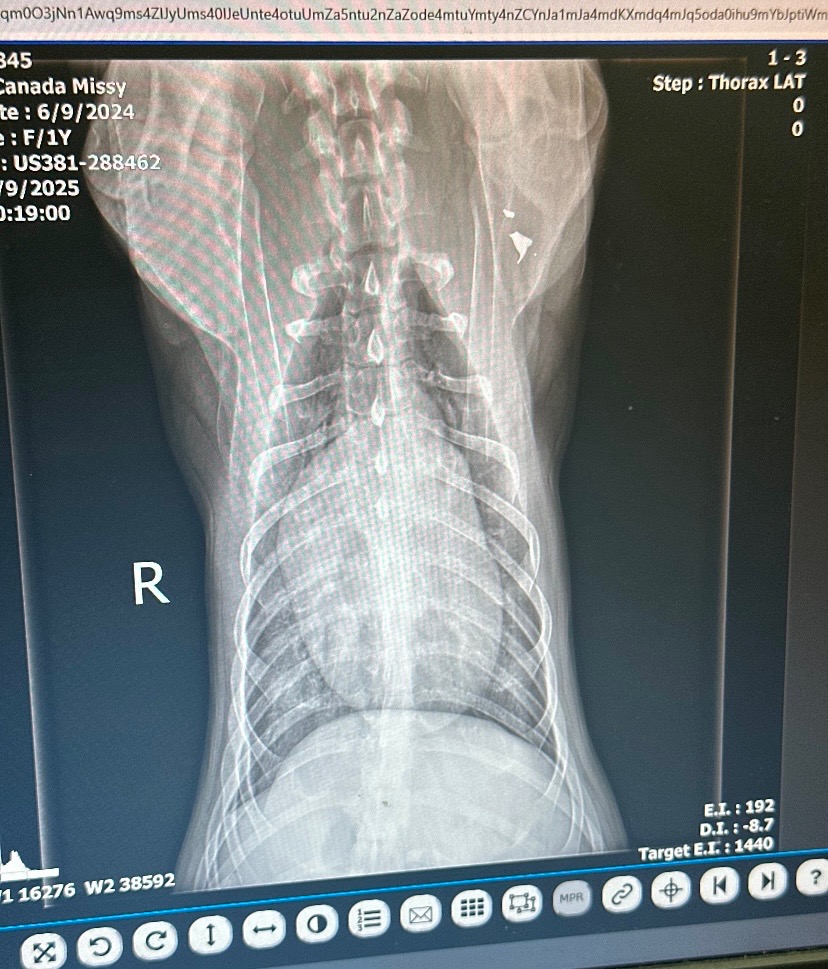

Missy, our one year old beautiful and very loved German Shepherd was shot by a very evil and cruel person with a .45 in the back and the bullet exited through her throat. She is a very loving and happy dog. She is not aggressive at all. Never meets a stranger!! Her jaw is severely fractured and dislocated. She needs to be transferred from Animal Emergency and Specialty to UT because they’re not comfortable doing the surgery. It will be a very complex and serious surgery. She needs a dental surgeon to try to repair her jaw. She is completely healthy in her body and mind still. The surgery needs to be done as fast as possible due to the risk of infection. Without surgery, she will have to wear a muzzle and be gruel fed. If you want to make cash donations, you can drop it off to Francis at Fuzzy Buttz Pet Grooming in Dandridge TN. We have already paid 2500$ just to keep her alive. She’s still in ICU. She is a part of our family. Our kids adore Missy. Please help her if you can. Even if it’s just 5-10$ any amount will help. Thank you. God Bless!!